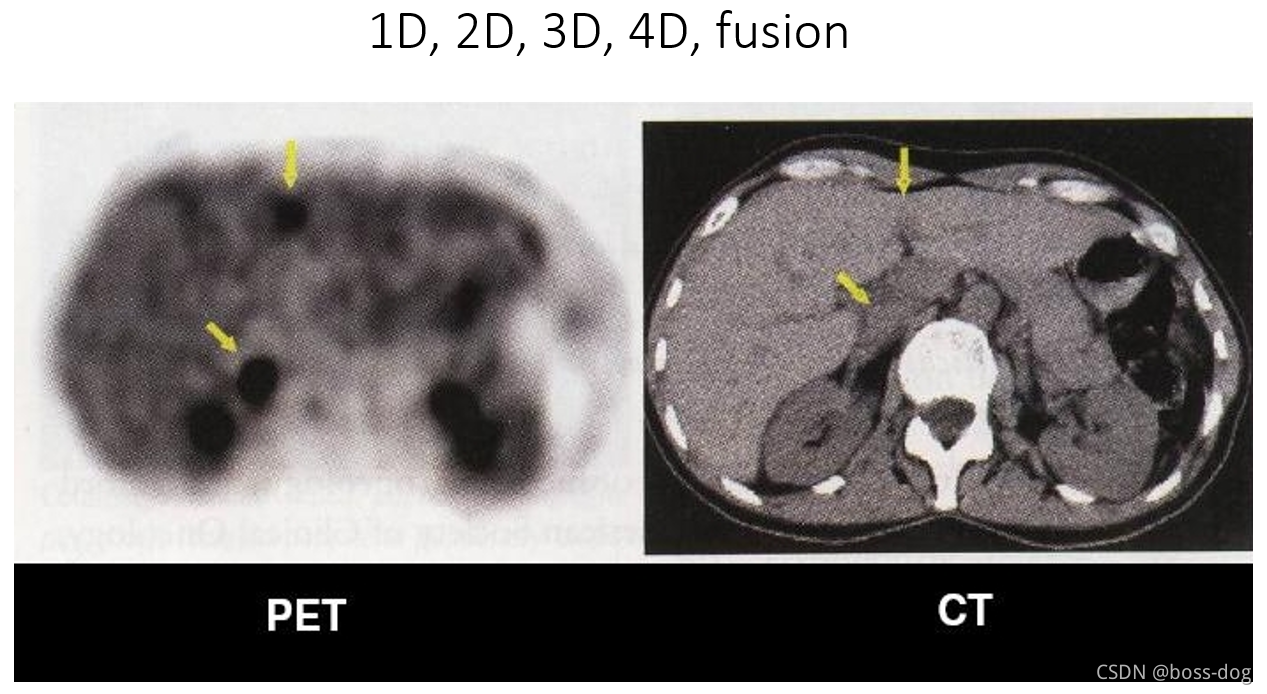

一维1D:比如抽血中的各项数指标、血压的数值等等、二维2D:比如心电图采集的图片记录下来的信息、DICOM图片等等、三维3D和四维4D的涉及一些动态图片比如后处理很酷炫的图片或分割的结果等等

上图中将两个图像进行一定的融合,左边PET的图像能够把肿瘤的位置给刻画出来,而CT能够把解剖的如人的骨头、肾、肝显示出来,两个图像进行修正和融合就可以看出来肿瘤到底在哪个位置,进行精准定位。